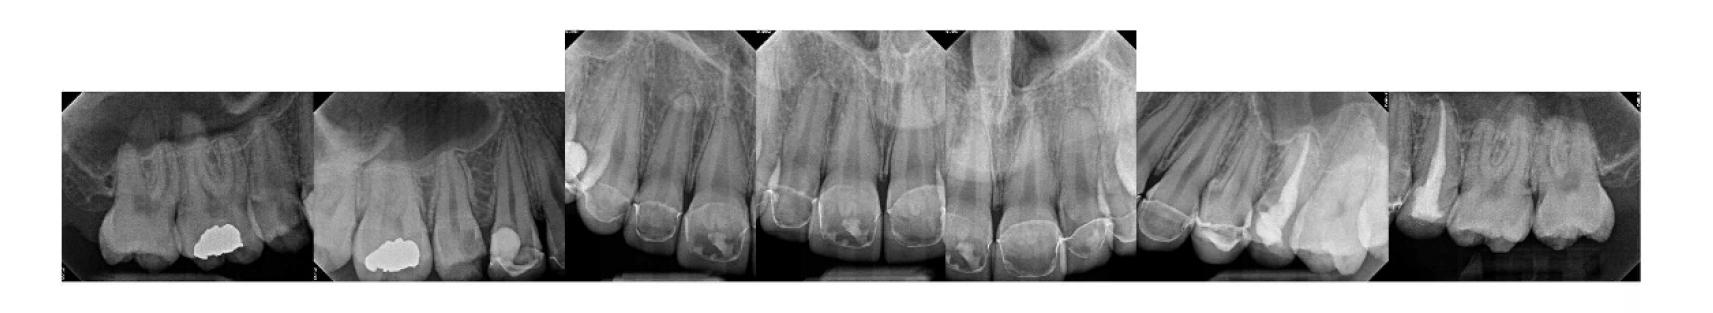

Figure 1. Example of characteristic Wickham striae and reticular pattern on buccal mucosa used to clinically diagnose OLL and OLP cases. Erythematous areas also seen. Figure 2. Frequency and percent of study patients using specific medications with color-coded drug classes.

Figure 3. Frequency of hypertension medications by specific classes.

The most common medication taken among subjects was metformin, comprising 24.6% (n=40). The most common phar macologic class was statin medications, at 36.4% (n=59); specifi cally, 15% (n=25) of patients took atorvastatin and 9% (n=15) took simvastatin. We also discovered that 17.9% (n=29) took proton-pump inhibitors and, interestingly, 16.7% (n=27) took le vothyroxine. These results are summarized in Figure 2 and Table 1.

Antihypertensives were the most common therapeutic class of medications among our subjects, at 49.4% (n = 80). As seen in Fig ures 2 and 3, when hypertension medications (color-coded green) are further subdivided into pharmacologic classes, beta blockers were the most associated with OLL/OLP, followed closely by angiotensinII-receptor blockers (ARBs) and calcium channel blockers (CCB). The thiazides are the next frequent type of hypertension medications taken by our OLL/OLP patient cohort. To our knowledge, our study is the first to further subtype the large and diverse class of hyperten sion medications associated with oral lichenoid lesions.